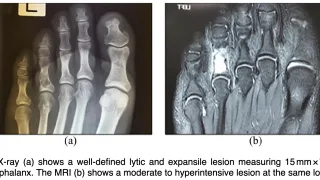

手術日+782日目 2026/4/20(月)(指骨骨髄炎)

午前の病院での仕事今朝は晴れ.気温は, 13 ℃と低めでした.8時前に病棟に上がって, 電子カルテを確認.昨晩は, 当院が整形外科の救急輪番でしたが, 救急車はゼロでした.夜勤だった後輩整形外科から電話連絡があり.隣の市から橈骨遠位端骨折の...